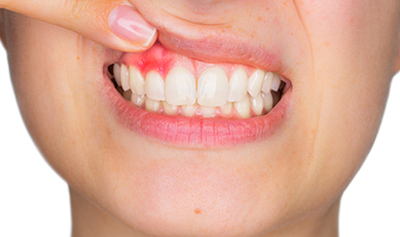

Periodoncia